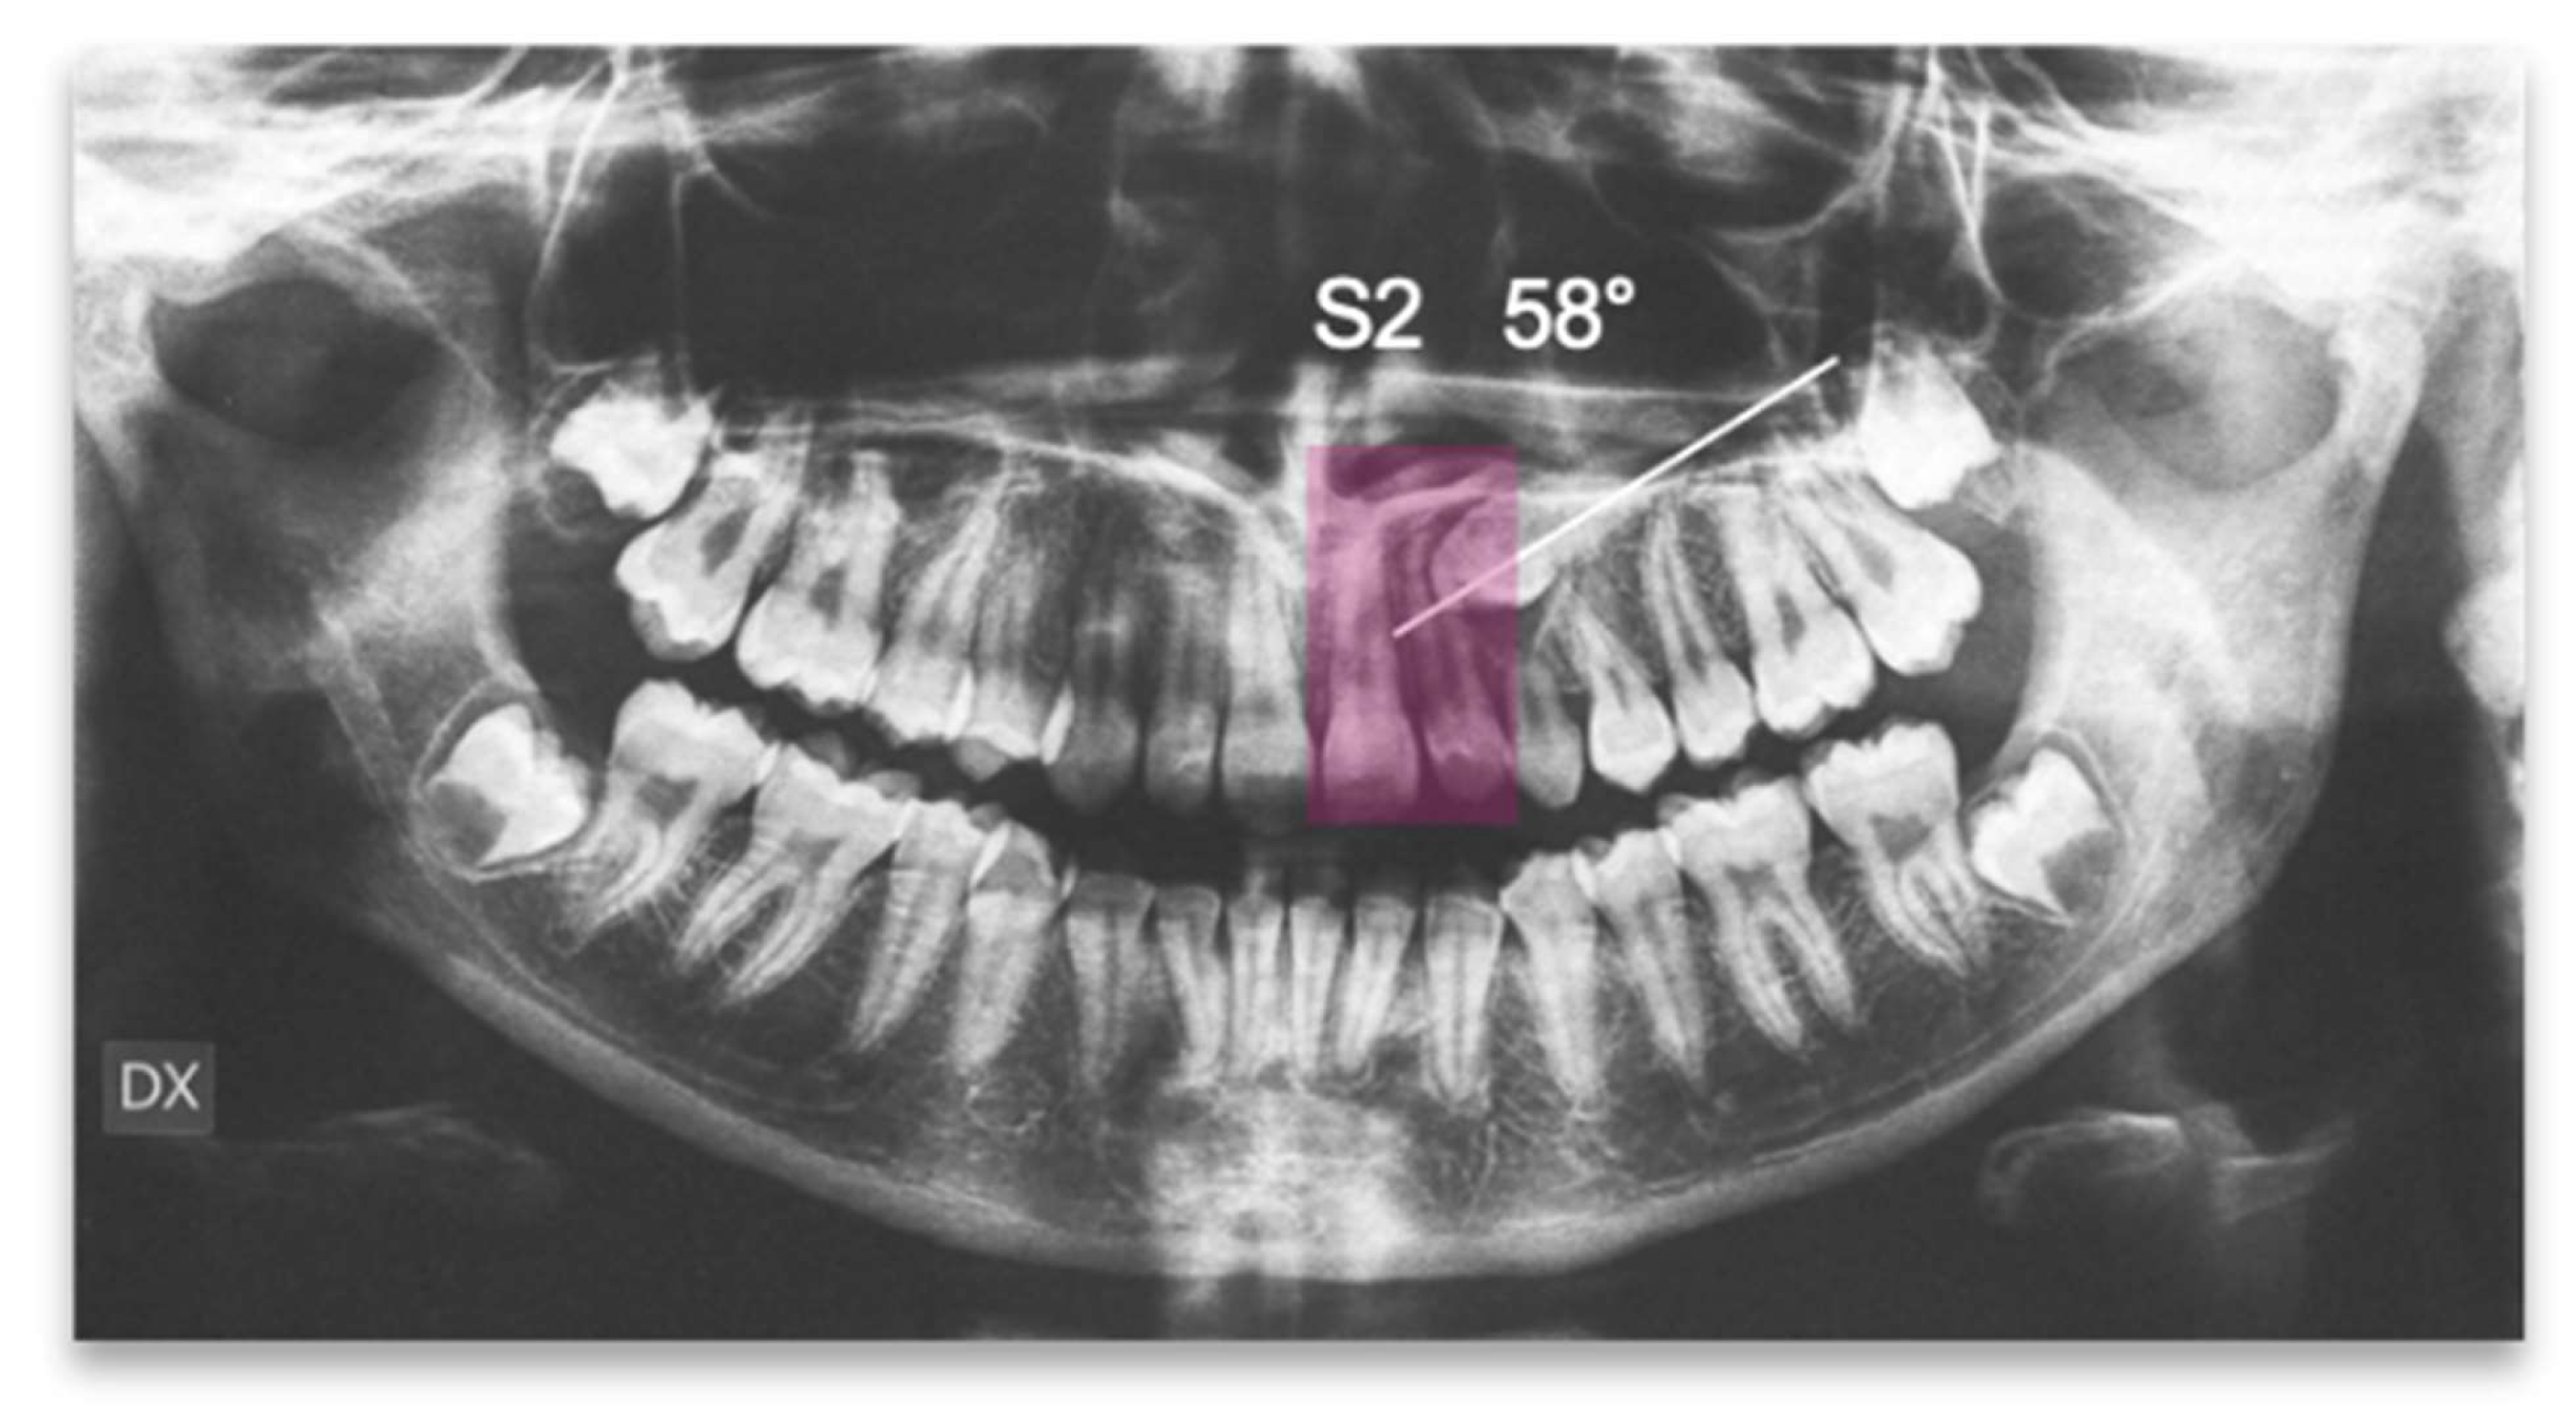

The position of the impacted canine showed an alpha angle of 58° and the Ericson and Kurol II sector classification. No clinical symptoms on articular examination were detected (Figure 12).

Figure 12.

Pre-treatment panoramic X-ray with the evaluation of alpha angle and sector according to the Ericson and Kurol classification.